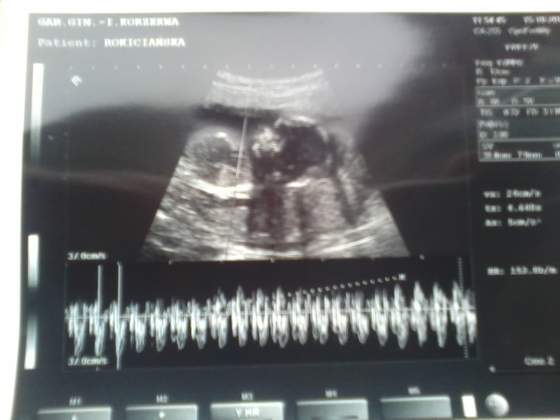

A to moje Motylki :-) przepraszam za kiepską jakość:zawstydzona/y:

14tc razem.jpg14tc ser1.jpg14tc ser2.jpg